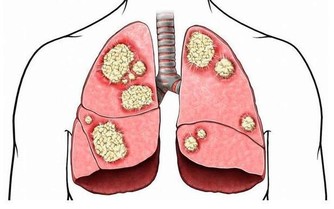

給肺部排毒——蒲公英桂花茶+合谷穴

有毒表現:皮膚呈銹色,晦暗。便秘。多愁善感,容易悲傷。

排毒茶:取蒲公英葉2.0g、綠茶龍井0.8g、桂花0.2g做成蒲公英桂花茶包,每日一包,熱水代茶飲即可。

蒲公英可清火利尿,消炎殺菌,緩解咽炎;桂花止咳化痰、養聲潤肺,解除口乾舌燥、腸胃不適、除口腔異味、並可滋潤皮膚。綠茶龍井可抗氧化,抗腫瘤,抗菌、抗產物過敏, 作為日常潤肺排毒代茶飲是不錯的選擇!

排毒穴:此穴可鎮靜止痛,通經活經,清熱解表。